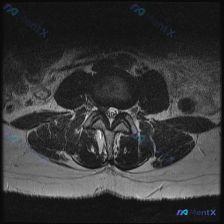

腰椎MRI轴位片读片分享:这个椎间盘病变很典型,你能读出关键点吗?

看到一张很典型的腰椎MRI轴位片,关于椎间盘病变的观察,整理了完整读片思路和分析,分享给大家。

这是一张腰椎MRI的T2加权轴位图像,层面为腰椎间盘水平。

- 椎间盘结构:中心前方的椎间盘T2信号较正常髓核降低,呈灰黑色,提示椎间盘脱水退行性改变

- 突出情况:椎间盘后缘可见局限性软组织信号影向后突出,分布为中线偏左侧,直接压迫推挤硬膜囊前缘,导致硬膜囊变形

- 侧隐窝与椎间孔:左侧侧隐窝受突出物影响,硬膜囊前间隙变窄,右侧侧隐窝开放状态良好

- 其他结构评估:黄韧带未见明显增厚,双侧关节突关节无显著骨质增生或关节间隙狭窄,椎旁肌结构对称无异常信号,中央椎管无显著狭窄,马尾神经束清晰可见

结合这张单一层面的影像,最符合的判断是腰椎退行性椎间盘疾病伴局限性偏左侧椎间盘突出,突出已经造成左侧侧隐窝狭窄、硬膜囊受压,但中央椎管尚无显著狭窄。